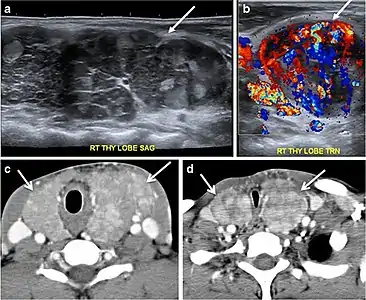

Fig. 9. A 58-year-old male patient with persistence PTC at thyroid bed with hypervascular nodal metastasis. a–c Transverse greyscale and colour Doppler neck ultrasound demonstrate hypoehoic soft tissue in the left thyroid bed (white arrow in a). There are a heterogeneous enlarged lymph nodes at level 2 and 3 with markedly increased vascularity (white arrow in b and c). d–f Enhanced axial CT images of the neck demonstrate a 2.7 × 1.4 cm hypodense soft tissue lesion anterior to the left carotid sheath (white arrow). There are left-sided enhancing abnormal and enlarged lymph nodes at cervical level 2 and 3 (black arrows).[1]

Fig. 14. A 19-year-old male patient known to have multi-nodular goiter and FNA, showing underlying Hashimoto's thyroiditis. a, b Sagittal and transverse greyscale and colour Doppler ultrasound of the neck demonstrate a hypoechoic enlarged right thyroid lobe with small hyperechoic regenerative nodules and marked hypervascularity (white arrows). c, d Enhanced axial CT scan images of the neck demonstrate a heterogeneously enhancing and enlarged thyroid gland, left more than right lobe, and the trachea is markedly narrowed.[1]